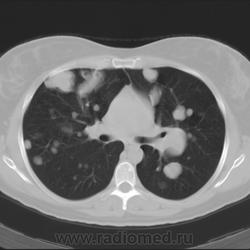

Рентгенологическая картина лейомиоматоза легких проявляется наличием в легочной ткани неоднородных очагов и фокусов уплотнения с четкими контурами (Рис.1.) число и размеры, которых могут постепенно увеличиваться.

Рис. 1. Лейомиоматоз легких.

Обзорная рентгенограмма органов грудной клетки. В легких с обеих сторон преимущественно в нижних отделах множественные разных размеров фокусы уплотнения, неоднородной структуры, с четкими контурами.

Компьютерные томограммы легких. В обоих легких множественные очаги и фокусы уплотнения разных размеров с четкими контурами. В толще неоднородной структуры фокусов выявляются неправильной формы полостные образования.